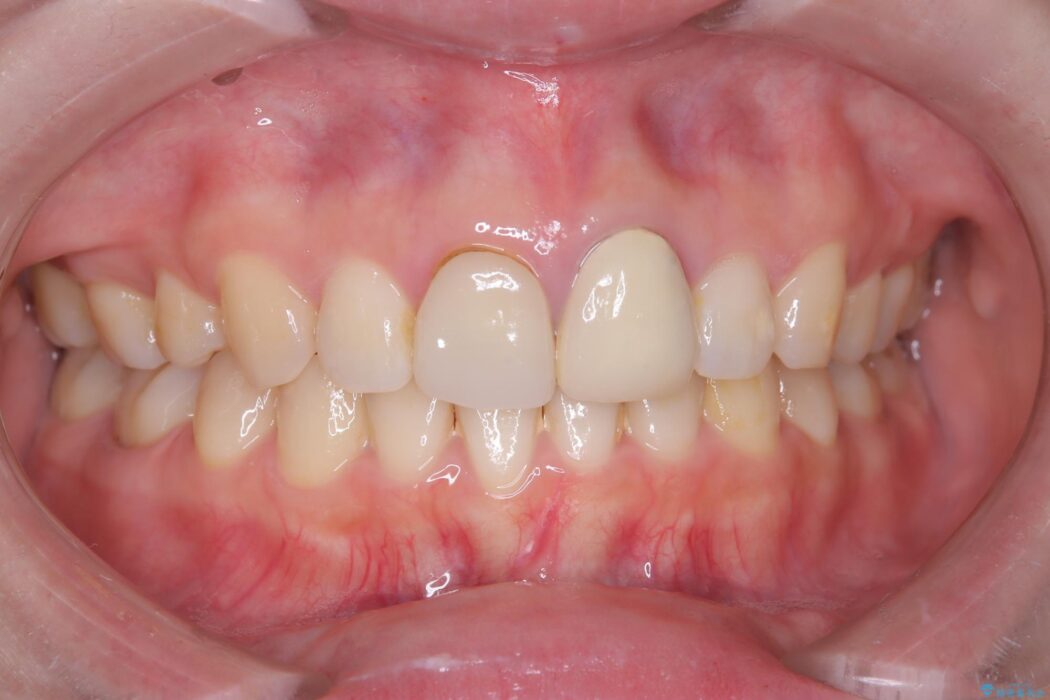

以前に他院で治療した前歯の見た目に不満があるとご来院された患者様です。

治療は、再感染の原因となっていた粗な根管充填材を丁寧に取り除く精密根管治療から開始しました。治療中はラバーダムと歯科用顕微鏡を使用し、根管内を徹底的に清掃・消毒。根の先まで緊密に薬を詰めることで、再発リスクを最小限に抑えました。根管治療の完了後、歯ぐきの状態を整え、周囲の歯と調和するオールセラミッククラウンを作製。金属を一切使わないため、透明感のある自然な仕上がりとなり、長年の見た目のコンプレックスも解消。歯の内部から表面までを根本的に改善することができました。